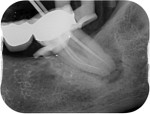

- Pathology on an x-ray (an area of infection)

On the second appointment we do the same procedure with local anaesthetic and disinfect and prepare the canals, once we are happy with our preparation the canals are sealed with rubber points and a sealant into each canal. Radiographs may be taken to check our progress before sealing. A temporary restoration may be placed depending if the tooth requires further treatment.

A follow up x-rays is normally taken a year after completion to ensure any areas of infection are healing.